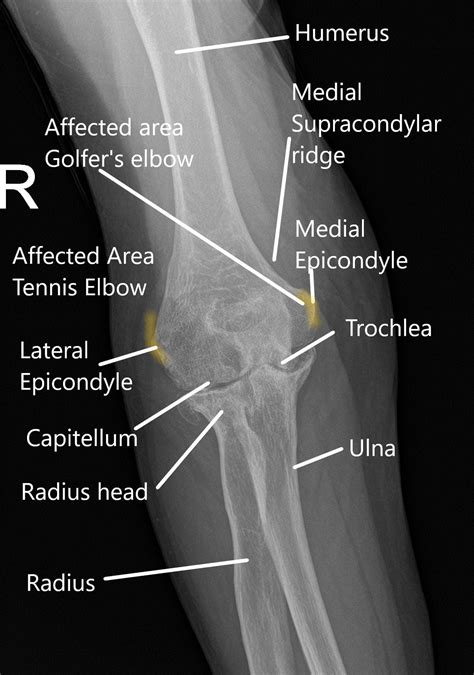

The elbow joint is a hinge joint that allows for flexion and extension of the forearm. It is formed by the articulation of three bones: the humerus, ulna, and radius. The humerus is the long bone of the upper arm, while the ulna and radius are the bones of the forearm.

• Humerus: The upper arm bone that forms the upper part of the elbow joint.

• Ulna: The larger of the two forearm bones, which forms the medial (inner) part of the elbow joint.

• Radius: The smaller of the two forearm bones, which forms the lateral (outer) part of the elbow joint.

Tendonitis is the inflammation of the tendons, which are the fibrous cords that attach muscles to bones. In the elbow, tendonitis commonly affects the tendons on the outer side of the elbow (lateral epicondylitis or tennis elbow) or the inner side (medial epicondylitis or golfer's elbow).

• elbow bones diagram

• elbow joint anatomy labeled

• elbow diagram

• elbow joint structure diagram